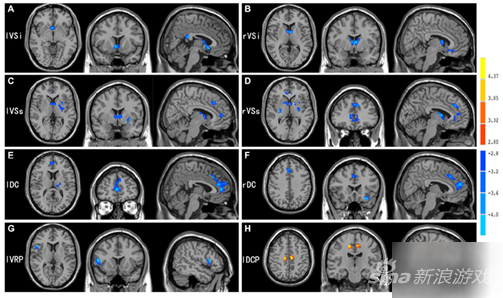

该研究运用功能连接方法对青少年网瘾患者静息态脑功能磁共振图像进行了分析,发现患者皮层-纹状体神经环路存在功能连接异常,且异常程度与患者的网瘾程度和焦虑行为等显著相关。

对比文献结果发现,青少年网瘾患者该环路的功能连接异常模式与鸦片等物质成瘾有类似之处。皮层-纹状体神经环路主要负责自主运动的控制、整合调节细致的意识活动和运动反应等功能,同时还与奖赏、情感、执行和控制等高级认知功能有关。